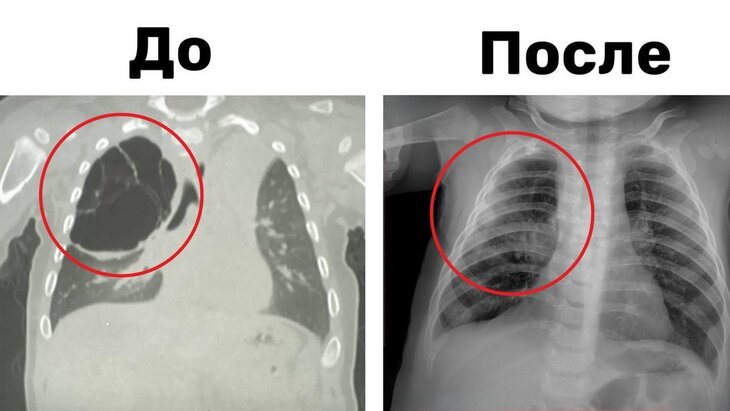

Новости здравоохраненияПодмосковные хирурги удалили ребенку кисту легкого размером 15 сантиметров

По информации ведомства, в результате обследования врачи обнаружили у ребенка 15-сантиметровую кисту, занимавшую значительную часть верхней доли правого легкого. Новообразование сдавливало здоровую ткань органа, что мешало его полноценному росту и развитию.

Хирурги приняли решение о проведении торакоскопической операции, в ходе которой им смогли удалить кисту без внешних разрезов. Продолжительность вмешательства составила около часа. В данный момент мальчик чувствует себя хорошо и уже выписан домой.